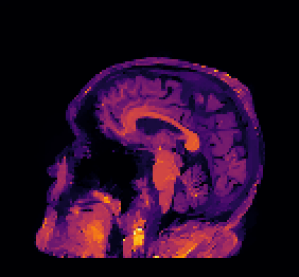

In multi-modality imaging one is often in possession of a specific piece of prior knowledge, namely a side information v𝑣v which is known to have some “common structure” with the true solution u𝑢u of the inverse problem [4]. The literature on this topic is rich with some works as early as the 1990’s so we only list a couple of key papers here. For instance, v𝑣v could be a high-resolution photograph which assists the reconstruction of low-resolution hyperspectral images [5, 6, 7, 8, 9] or an anatomical (MRI or CT) image for the reconstruction of PET images [10, 11, 12, 13, 14, 15, 16, 17], see Figure 2. This strategy has also been used for functional MRI (fMRI) [18], spectral CT [19], electrical impedance tomography (EIT) [20] and multi-contrast MRI [21, 22, 23, 24, 25, 26].

Figure 1: In many applications two images of different contrast and resolution are acquired. Images courtesy of D. Coomes, P. Markiewicz and J. Schott.